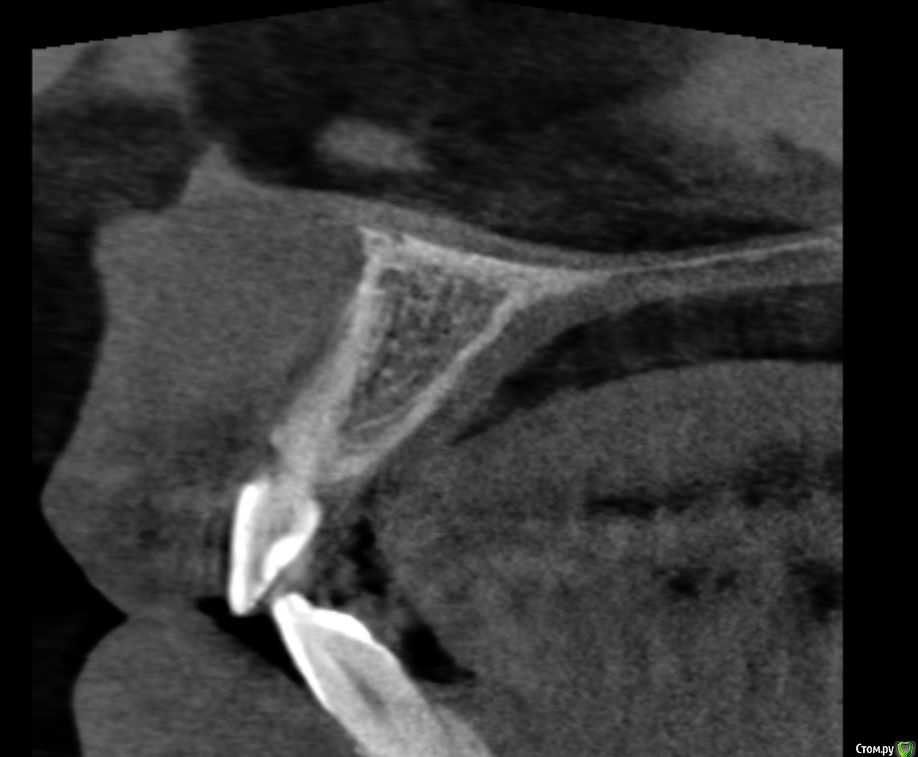

Lanasvlisa Опубликовано 21 апреля, 2017 Поделиться Опубликовано 21 апреля, 2017 Добрый вечер, уважаемые врачи! Вопрос по зубу 22, он леченый-перелеченный, сейчас на корне обнаружена киста, на десне над зубом свищевой ход. Какое ваше мнение: 1) удалять зуб и вместе с ним уйдет воспаление, прочищать все и заниматься имплантацией; или 2) можно каким-то образом удалить кисту, отсечь корень (читала о таком), но сам зуб не удалять? Если всё-таки 1), то можно ли осуществить в данном случае одномоментную имплантацию с нагрузкой? или можно одномоментную, но без нагрузки...? Спасибо огромное всем, кто посмотрит снимки и выразит свое экспертное мнение! С уважением, PS: прикрепляю скриншот из программы, но если этого недостаточно для определения диагноза и плана вмешательства, то скину ссылку на весь архив. Ссылка на комментарий

колесников Опубликовано 21 апреля, 2017 Поделиться Опубликовано 21 апреля, 2017 Резецировать там нечего,во время эндодонтического лечения произошла перфорация стенки корня зуба,вокруг этого участка очаг деструкции костной ткани. Это не лечится.По выставленной вами картинке объём деструкции не понятен. Решить возможность одномоментной имплантации и тем более немедленной нагрузки может только ваш лечащий доктор ,по результатам кт и в соответствии со своим опытом. Ссылка на комментарий

Lanasvlisa Опубликовано 22 апреля, 2017 Автор Поделиться Опубликовано 22 апреля, 2017 Здравствуйте, уважаемые врачи, и спасибо большое вам за оперативные ответы! Я не знаю, как найти срезы, полагаю, проекции - это то же самое, что и срезы? Я сделала их скриншоты+ еще три фото. А если я все-таки отправлю ссылку на весь архив, вы бы могли оценить объем разрушения костной ткани, чтобы предположить, насколько реально провести имплантацию в день удаления? У меня еще такие вопросы: если имплантацию удается провести сразу, то 1) через какой срок можно в моем случае заняться установкой коронки; 2) какая она должна быть; 3) если придется пользоваться "бабочкой" (я так понимаю, это единственный вариант, все временные коронки, в том числе клеевые, - это нагрузка, а каппа сюда тоже не подойдет?), то как потом происходит восстановление формы десны? Можно ли как-то сохранить десневые сосочки в случае отсроченной имплантации? Спасибо большое! Ссылка на комментарий